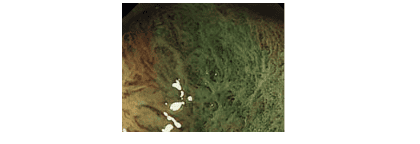

4. Đánh giá polyp qua nội soi phóng đại và nội soi nhuộm màu

Ngày nay, với sự ra đời của các thế hệ máy nội soi tiên tiến hơn, với chế độ nhuộm màu tổn thương bằng điện tử (chức năng NBI), chức năng phóng đại tổn thương lên 10 lần, 40 lần, 100 lần… ta có thể phóng đại tổn thương để đánh giá chi tiết hơn.

Dựa vào các mức độ biến dạng của bề mặt, biến dạng của mạch máu, các tác giả Nhật Bản đã có nhiều phân loại polyp: phân loại Sano, phân loại Hiroshima, phân loại Kudo, phân loại JNET, và thế giới cũng đã có phân loại NICE để đánh giá khả năng ác tính của polyp.

Đối với các polyp có vi bề mặt (quan sát trên nội soi phóng đại ) không đều, các vi mạch máu bề mặt dãn, xoắn, đứt đoạn, đường kính không đều… sẽ được phân loại vào dạng các polyp có nguy cơ xâm lấn xuống lớp dưới niêm, và việc cắt polyp qua nội soi sẽ không đảm bảo về phương diện ung thư.